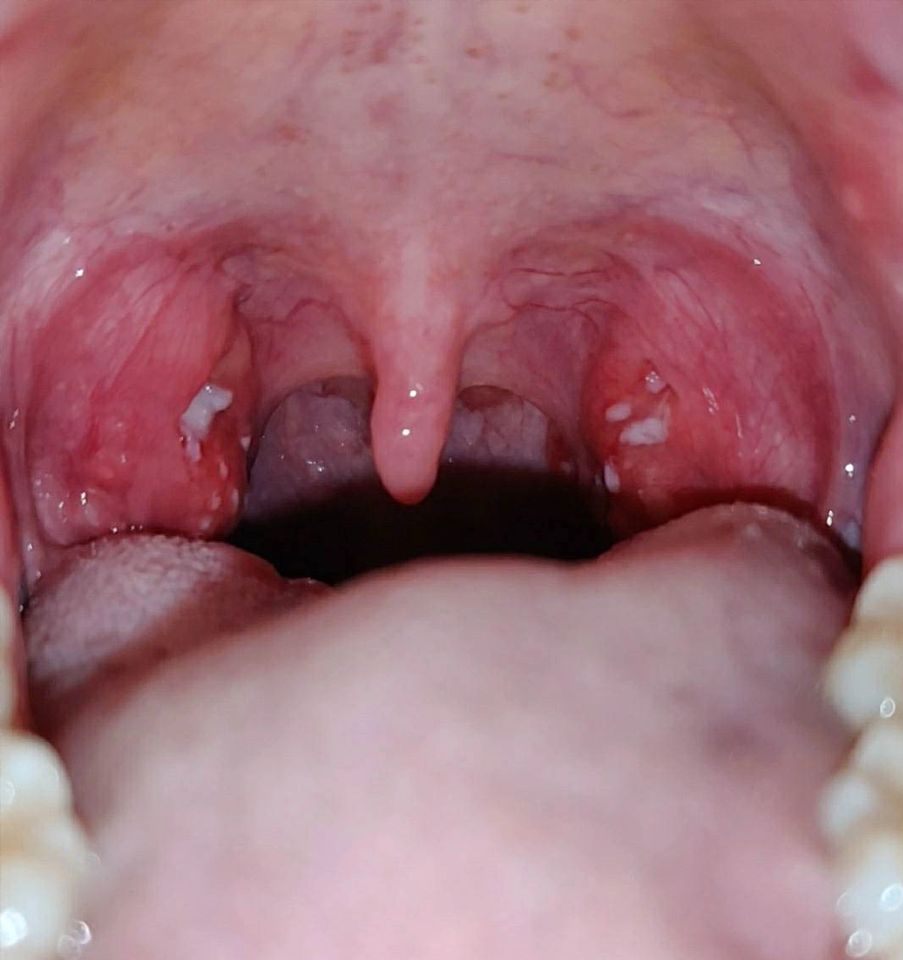

Φωτογραφίες πραγματικών περιστατικών από το εξεταστήριό μας

Στο ιατρείο του Τσιλιώνη Απόστολου, στην πόλη του Βόλου, πραγματοποιούνται εξετάσεις ΩΡΛ με προηγμένα ιατροτεχνολογικά μέσα για τη διενέργεια ελέγχου σε ποικίλους τομείς της Ωτορινολαρυγγολογίας και της Χειρουργικής.

Δείτε σχετικό φωτογραφικό υλικό από περιστατικά ασθενών.